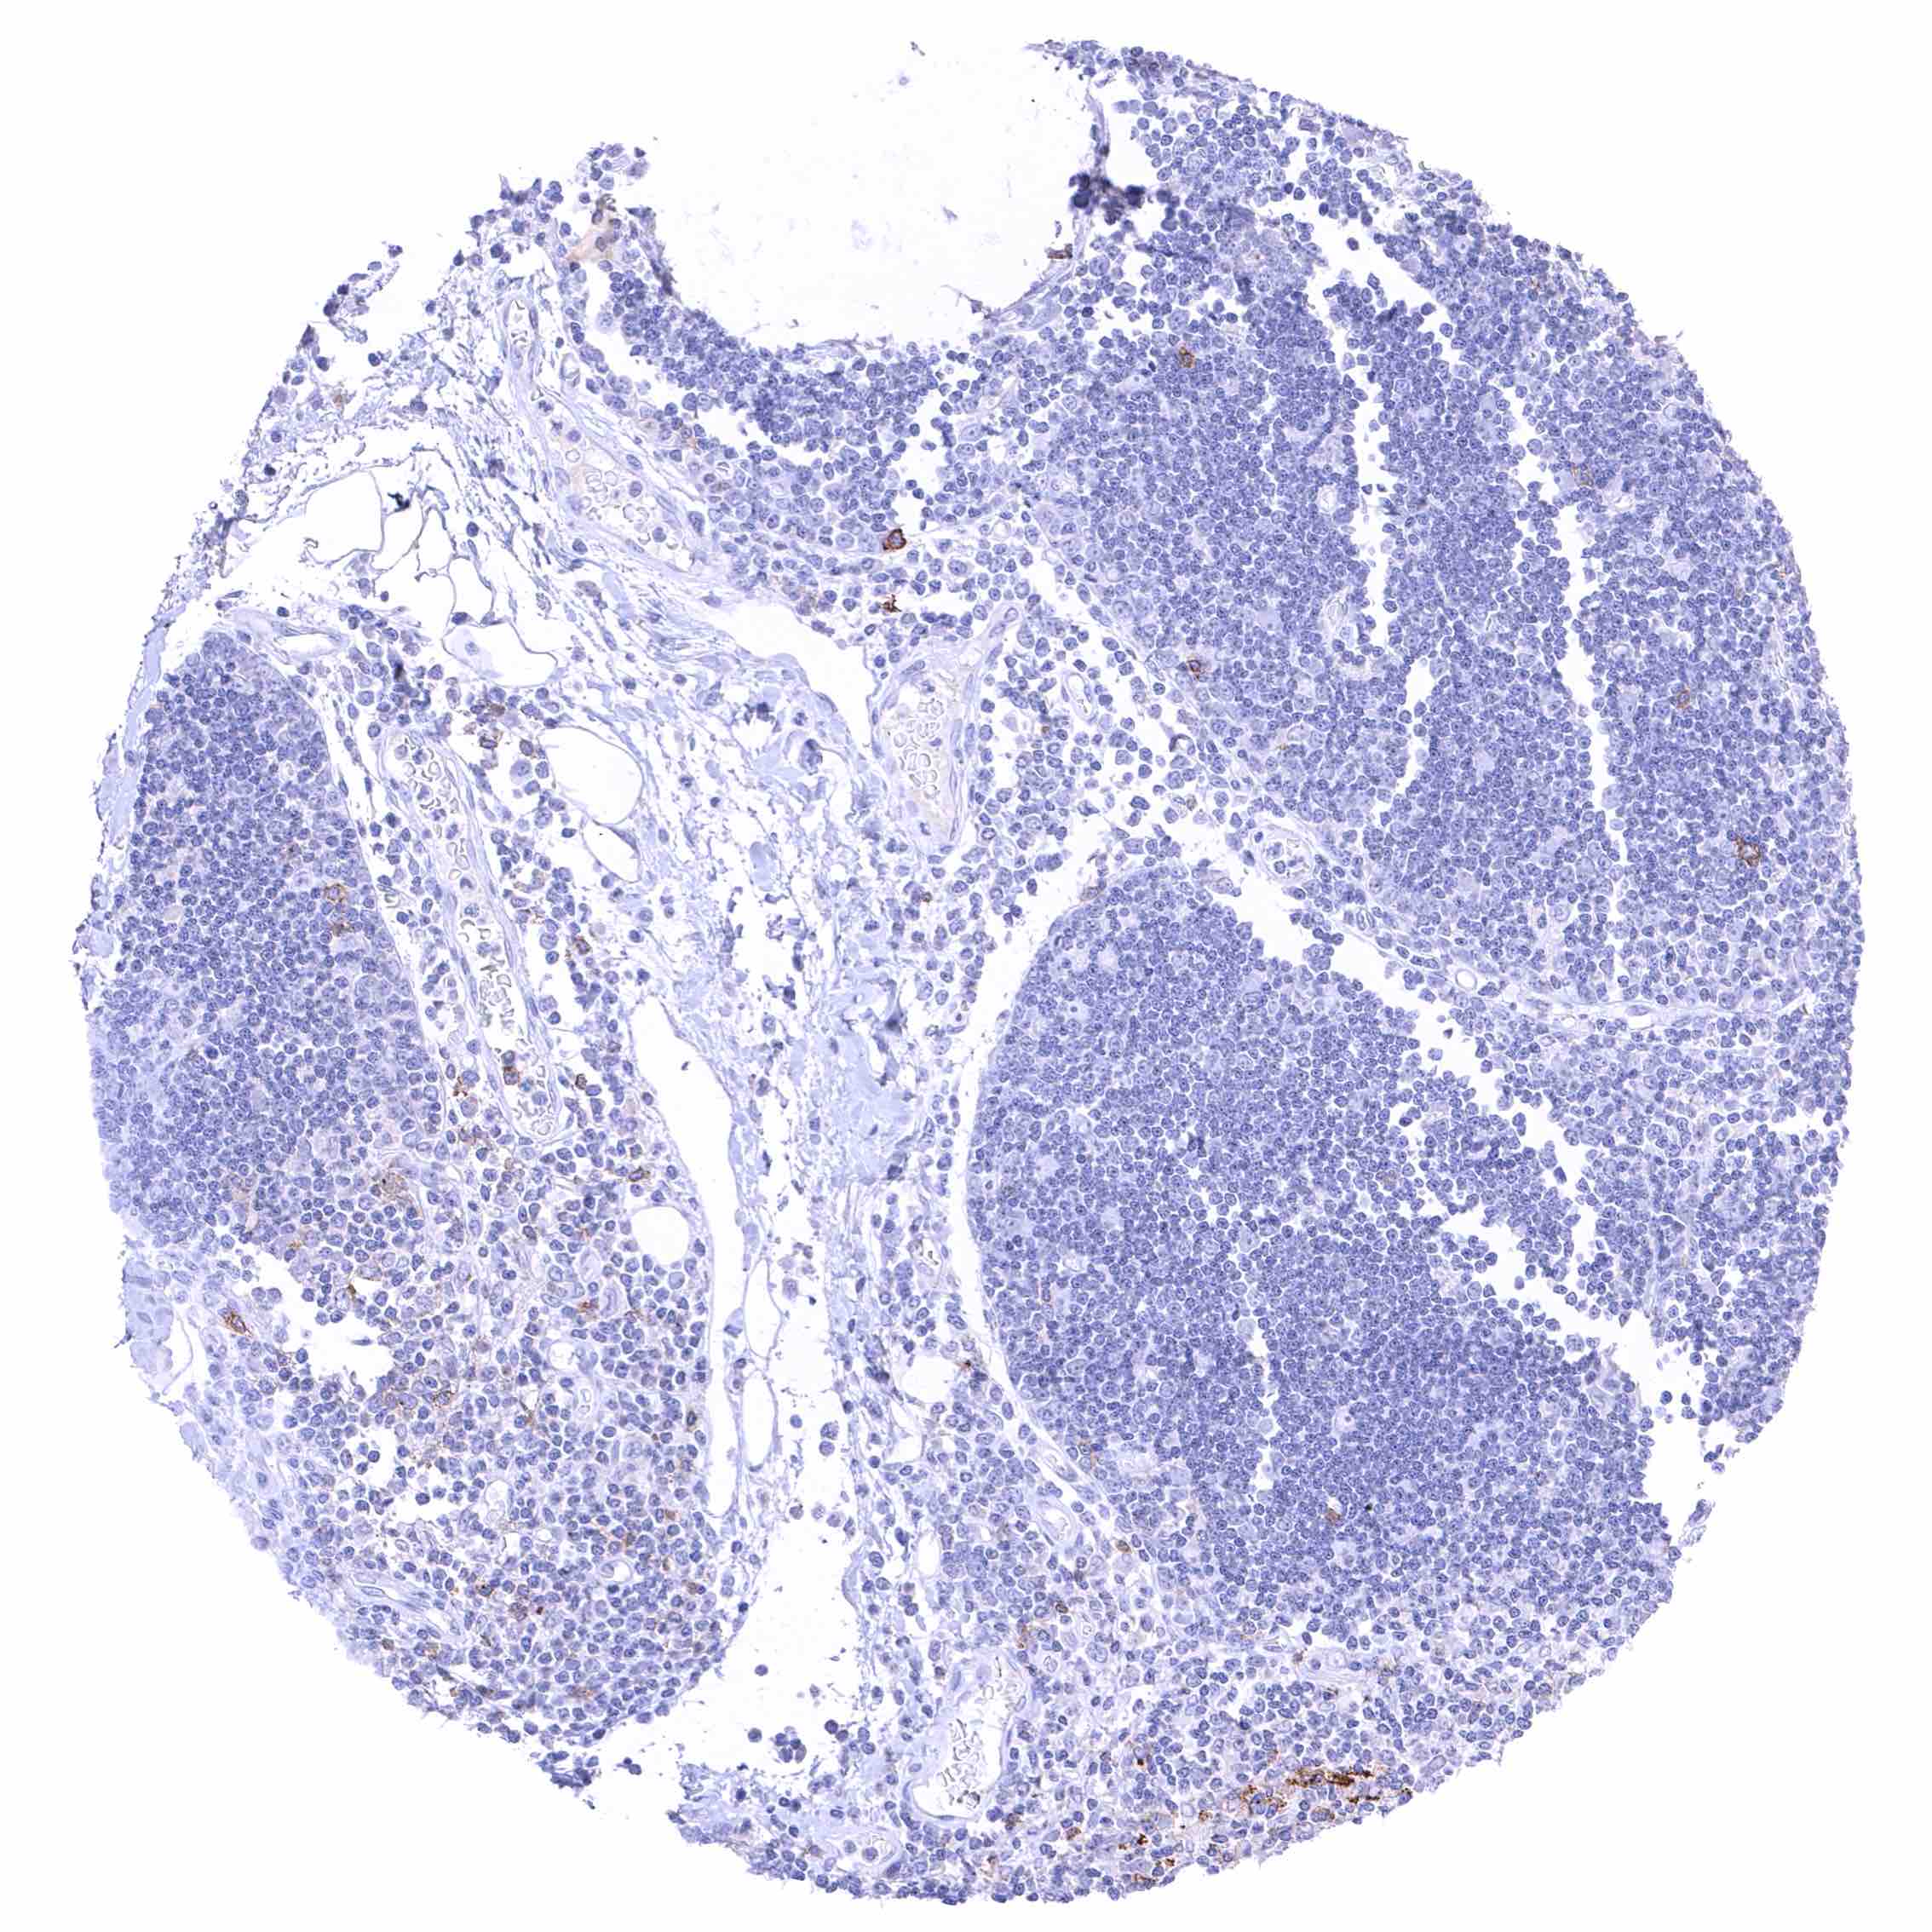

| Appendix | Distinct CD70 positivity of a fraction of lymphocytic cells, predominantly interfollicular. Epithelial cells are CD70 negative. | |

| Tonsil | Membranous CD70 staining of variable intensity in subsets of inflammatory cells (mostly lymphocytes). Most CD70 positive cells are interfollicular. Squamous epithelium remains CD70 negative. | |

Positive control = Appendix: A distinct membranous CD70 staining should be seen in a subset of inflammatory cells (especially interfollicular).

Negative control = Appendix: CD70 staining should be absent in epithelial cells.